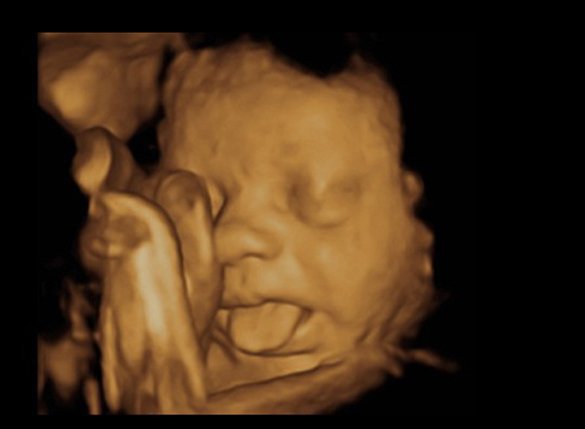

Dịch vụ siêu âm

Siêu âm là một kỹ thuật chẩn đoán hình ảnh không xâm lấn, sử dụng sóng siêu âm (sóng âm tần số cao) để xây dựng và tái tạo hình ảnh về cấu trúc bên trong cơ thể. Những hình ảnh này cung cấp thông tin có giá trị trong việc chẩn đoán và điều trị bệnh.

🌵 Đặc biệt, siêu âm sàng lọc các dị tật thai nhi là dịch vụ tạo ra thương hiệu Quang Khởi.